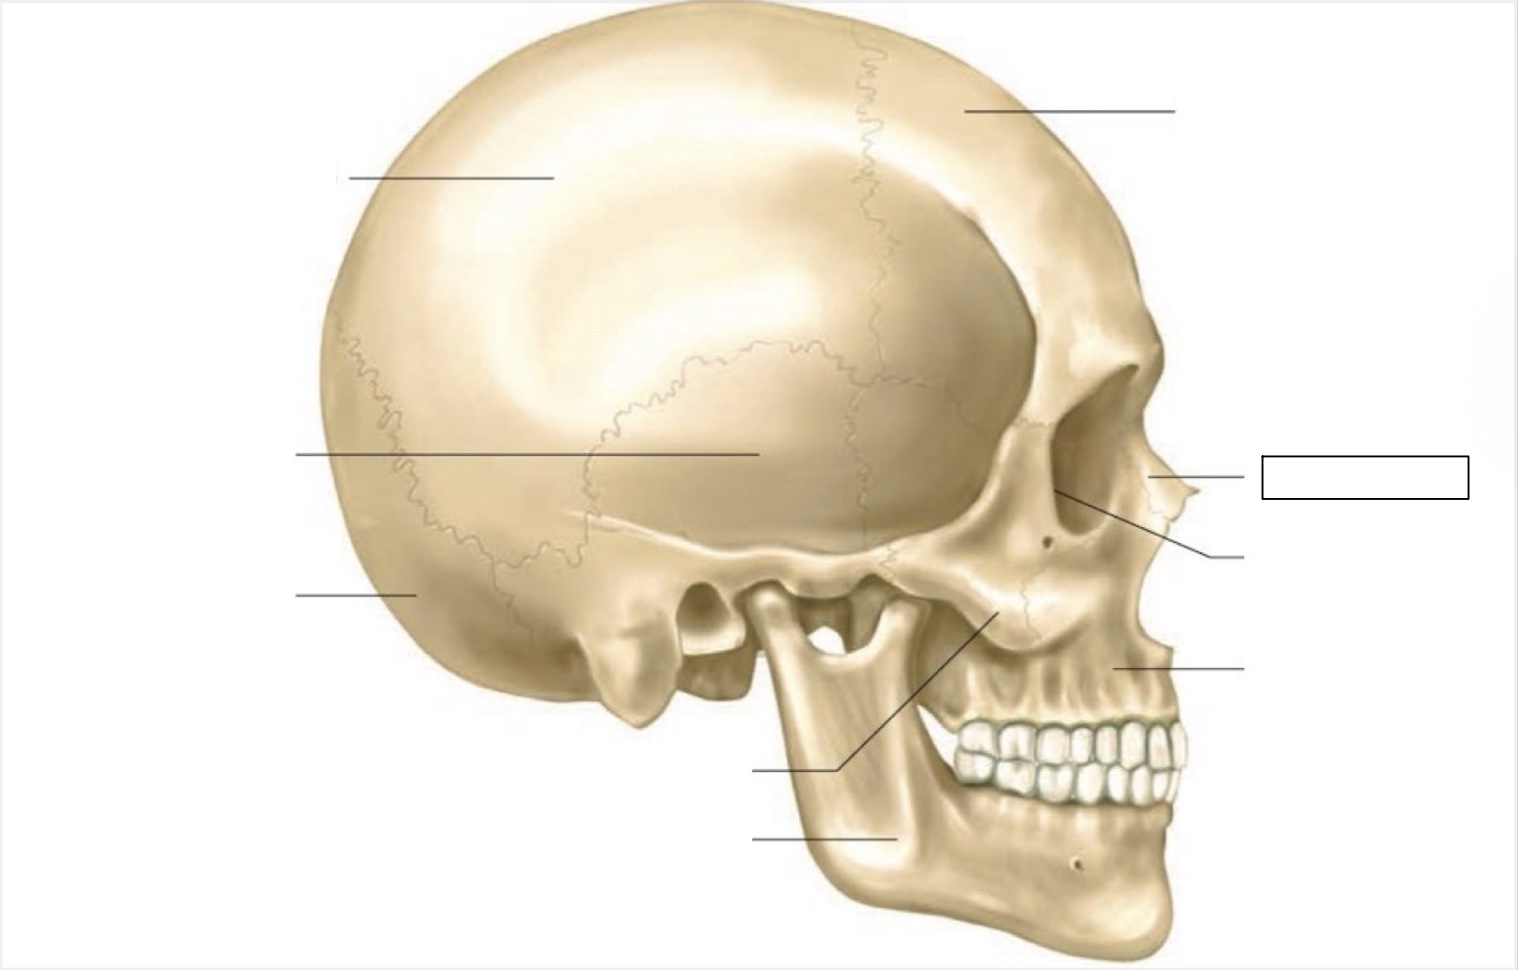

skull

frontal bone

nasal bone

orbit

maxilla

mandible

zygomatic bone

occipital bone

temporal bone

parietal bone